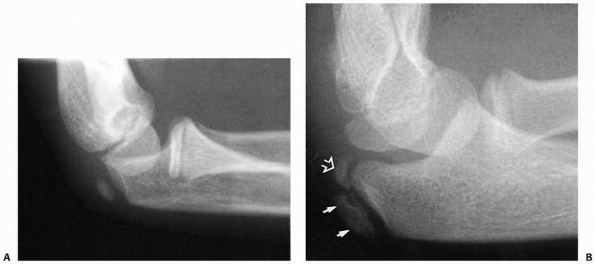

ulnar metaphysis. At birth, the ossification margin lies halfway

between the coronoid process and the tip of the olecranon. By about 6

or 7 years of age, it appears to envelop about 66% to 75% of the

capitellar surface. The final portion of the olecranon ossifies from a

secondary ossification center that appears around 6.8 years of age in

girls and 8.8 years in boys (Fig. 13-8A). Peterson38 described two separate centers: one articular and the other a traction type (Fig. 13-8B). This secondary ossification center of the olecranon may persist late into adult life.37

FIGURE 13-8 Ossification of the olecranon. A. Secondary ossification begins as an oblique oblong center at about 6 to 8 years of age. B. It may progress as two separate ossification centers: articular (open arrow) and traction (closed arrows).